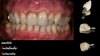

Patiente référée qui consulte pour des récessions tissulaires marginales associées à des sensibilités.

Un bilan parodontal est effectué puis on passe à la chirurgie gingivale.